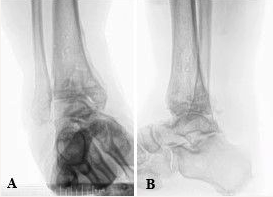

A 63-year-old man with right posttraumatic osteoarthritis was initially seen for constant ankle pain and paresthesia (Figure 1). The patient previously had a pilon fracture following a high-speed automobile accident. The fracture was repaired and fully healed with a posterior plate, medial plate, and screw fixation in the fibula (Figure 2). The patient adamantly declined undergoing AA because he wanted to maintain ankle mobility. Patient risk factors for poor peripheral circulation included a 10-pack-year smoking history, a body mass index of 37 kg/m2, and a medical history significant for chronic venous stasis, lymphedema, deep vein thrombosis, and hypertension. The listed risk factors caused him to be a poor surgical candidate, and TAA was relatively contraindicated. Additionally, on initial physical examination, he had visibly poor ankle integument, ankle hemosiderin deposits, and mild to moderate venous congestion.